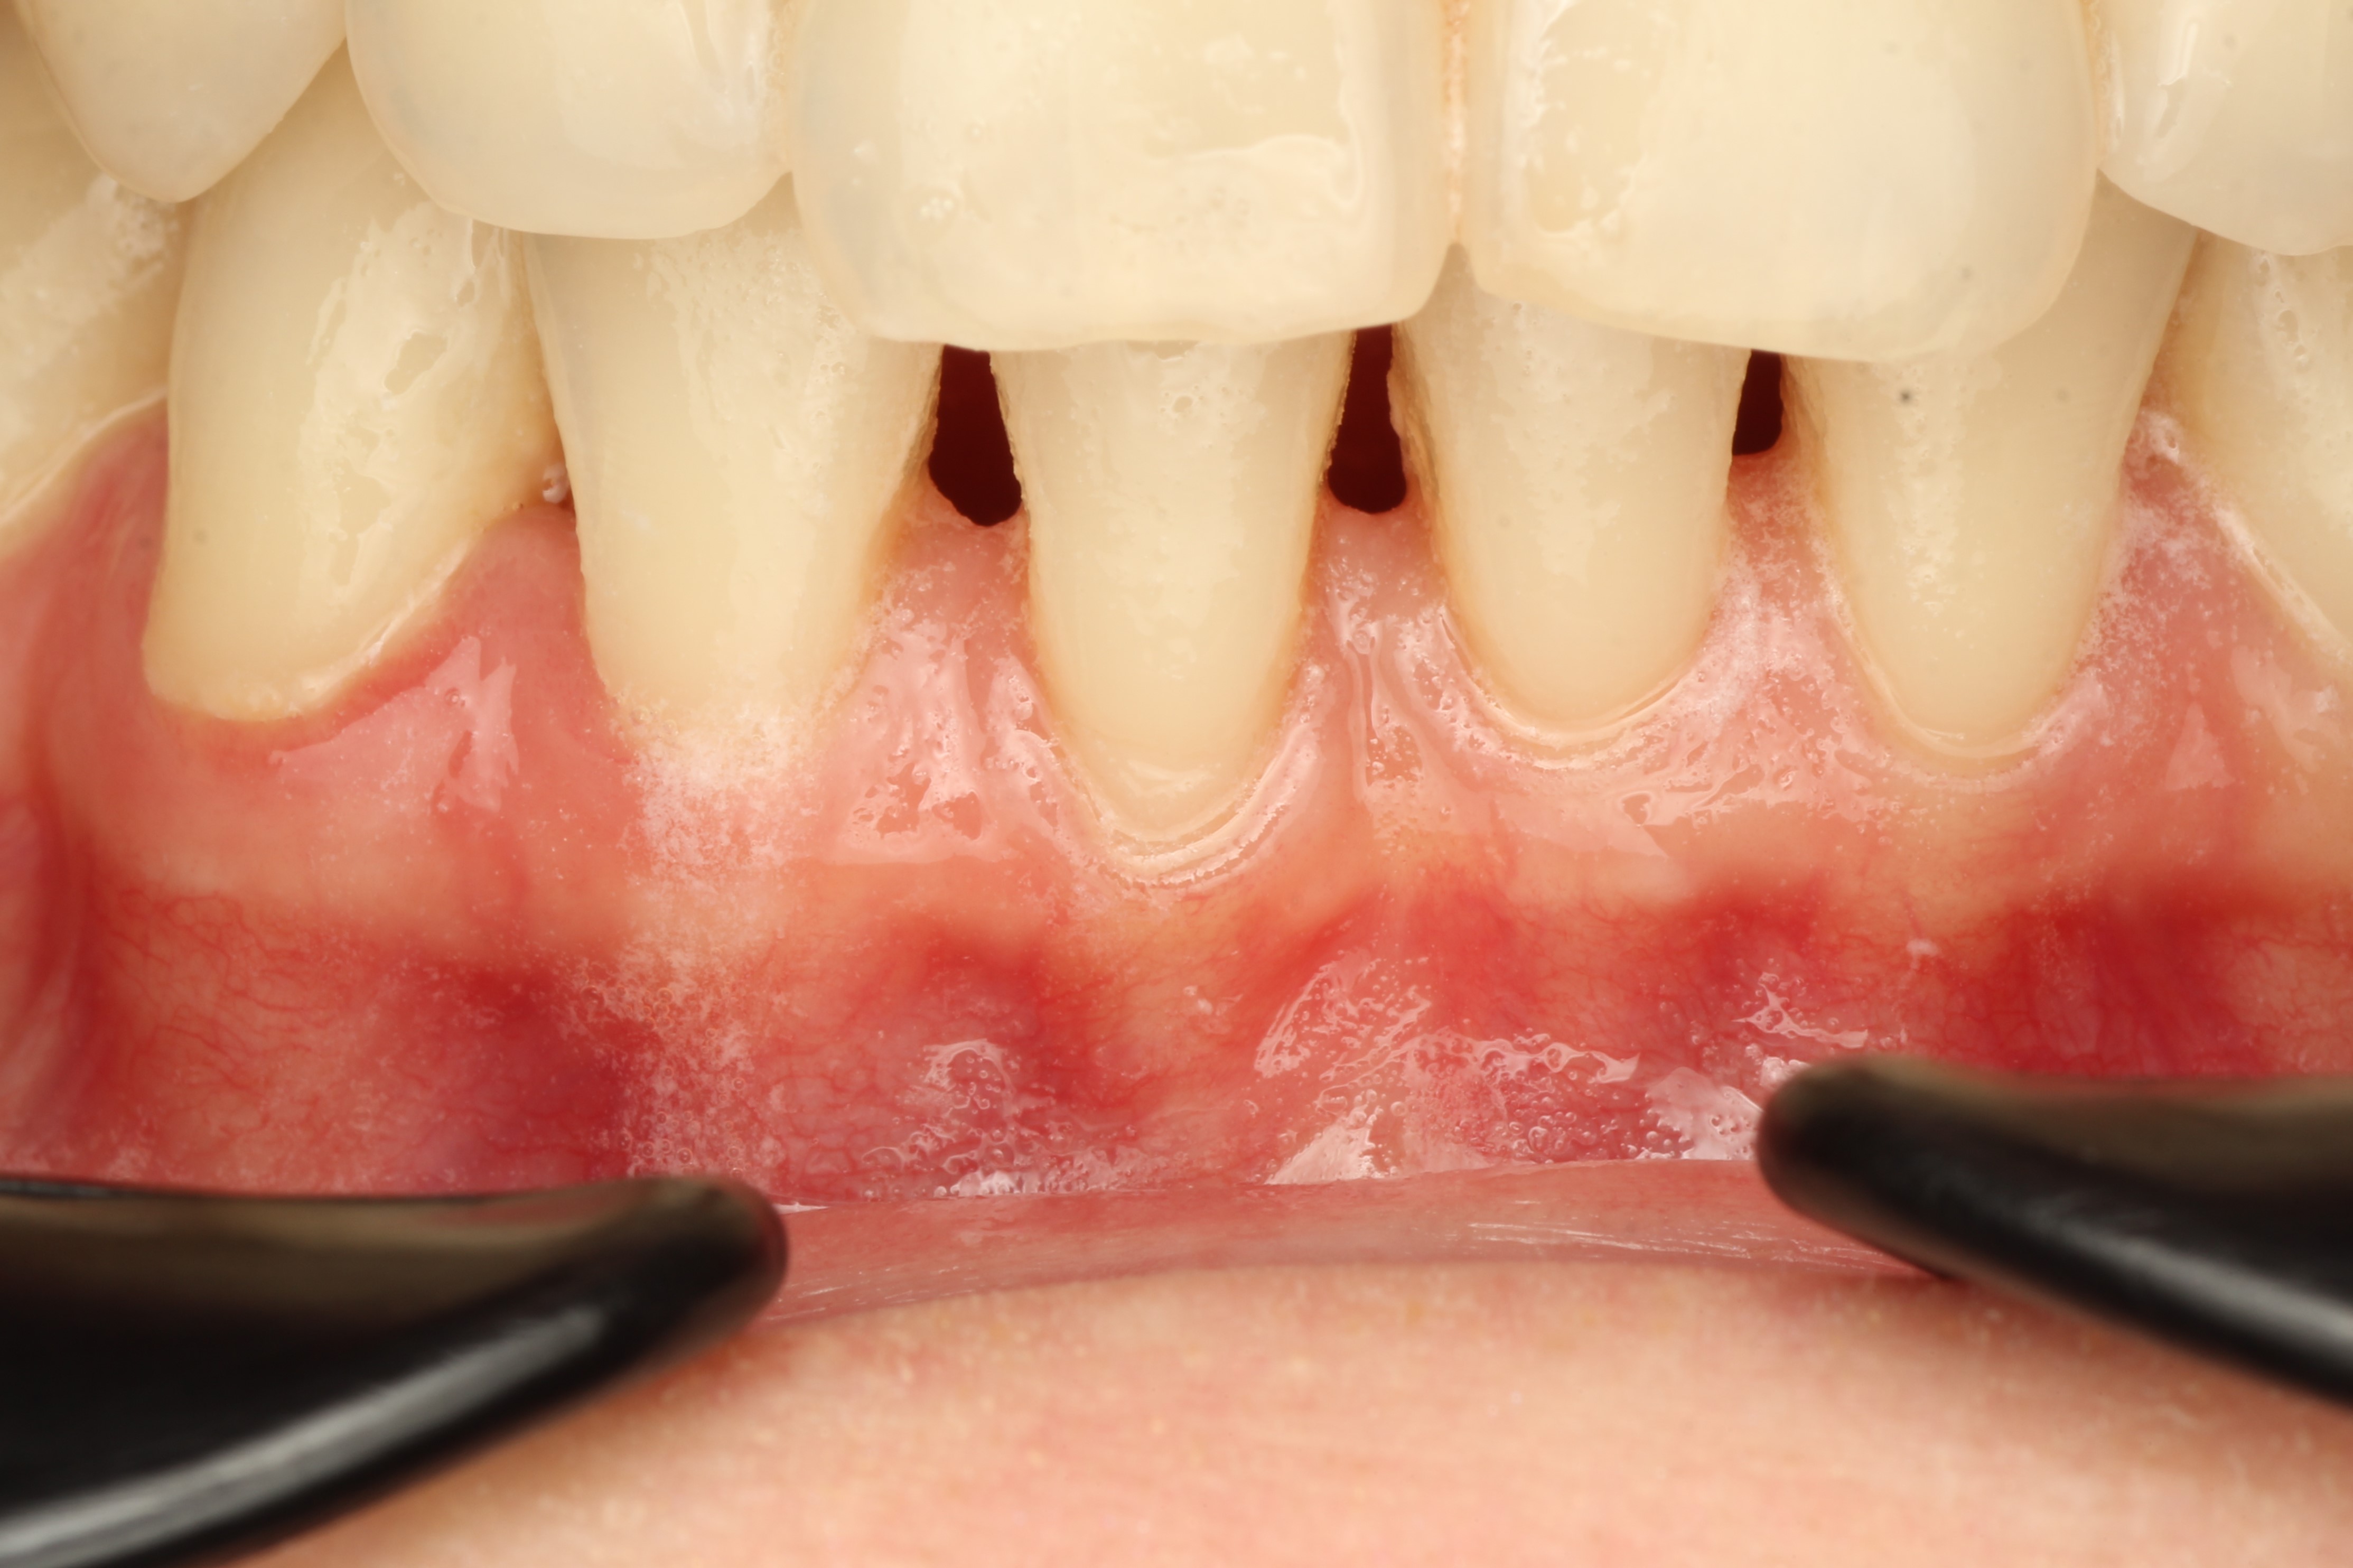

Через три года после операции результат стабилен, толщина мягких тканей достаточная, те из тонкого биотипа мы получили средний или толстый

Но при этом гигиена пациента остается неудовлетворительной.

На фотографии в боковой проекции мы видим полное закрытие оголенного корня, стабильный и долгосрочный результат.